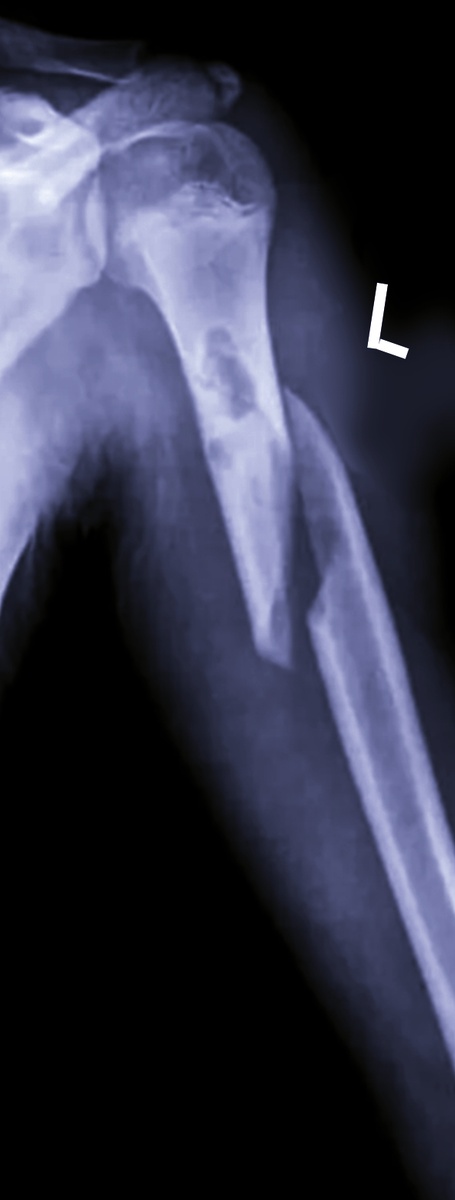

Бабулечка хрупкая, 82 года, был заметен перелом бедра и плеча, решила я ее не перекладывать, хватит на нее мощности аппарата.

При снимке легких решила и руку на кассету уместить, хотя бы на одну проекцию, но нагрузки меньше. Да, сломано плечо.

Попробовала чуть ротировать руку для другой проекции- сильно стонет. Ладно, пусть репозицию сделают, гипс наложат, тогда потом и две можно. Вряд ли ее в экстренные пациенты подадут, а для плановой пациентке все равно выполнят гипсовую иммобилизацию.

Да , и бедро тоже сломано. Все с левого бока.

Да, перелом плеча тоже.